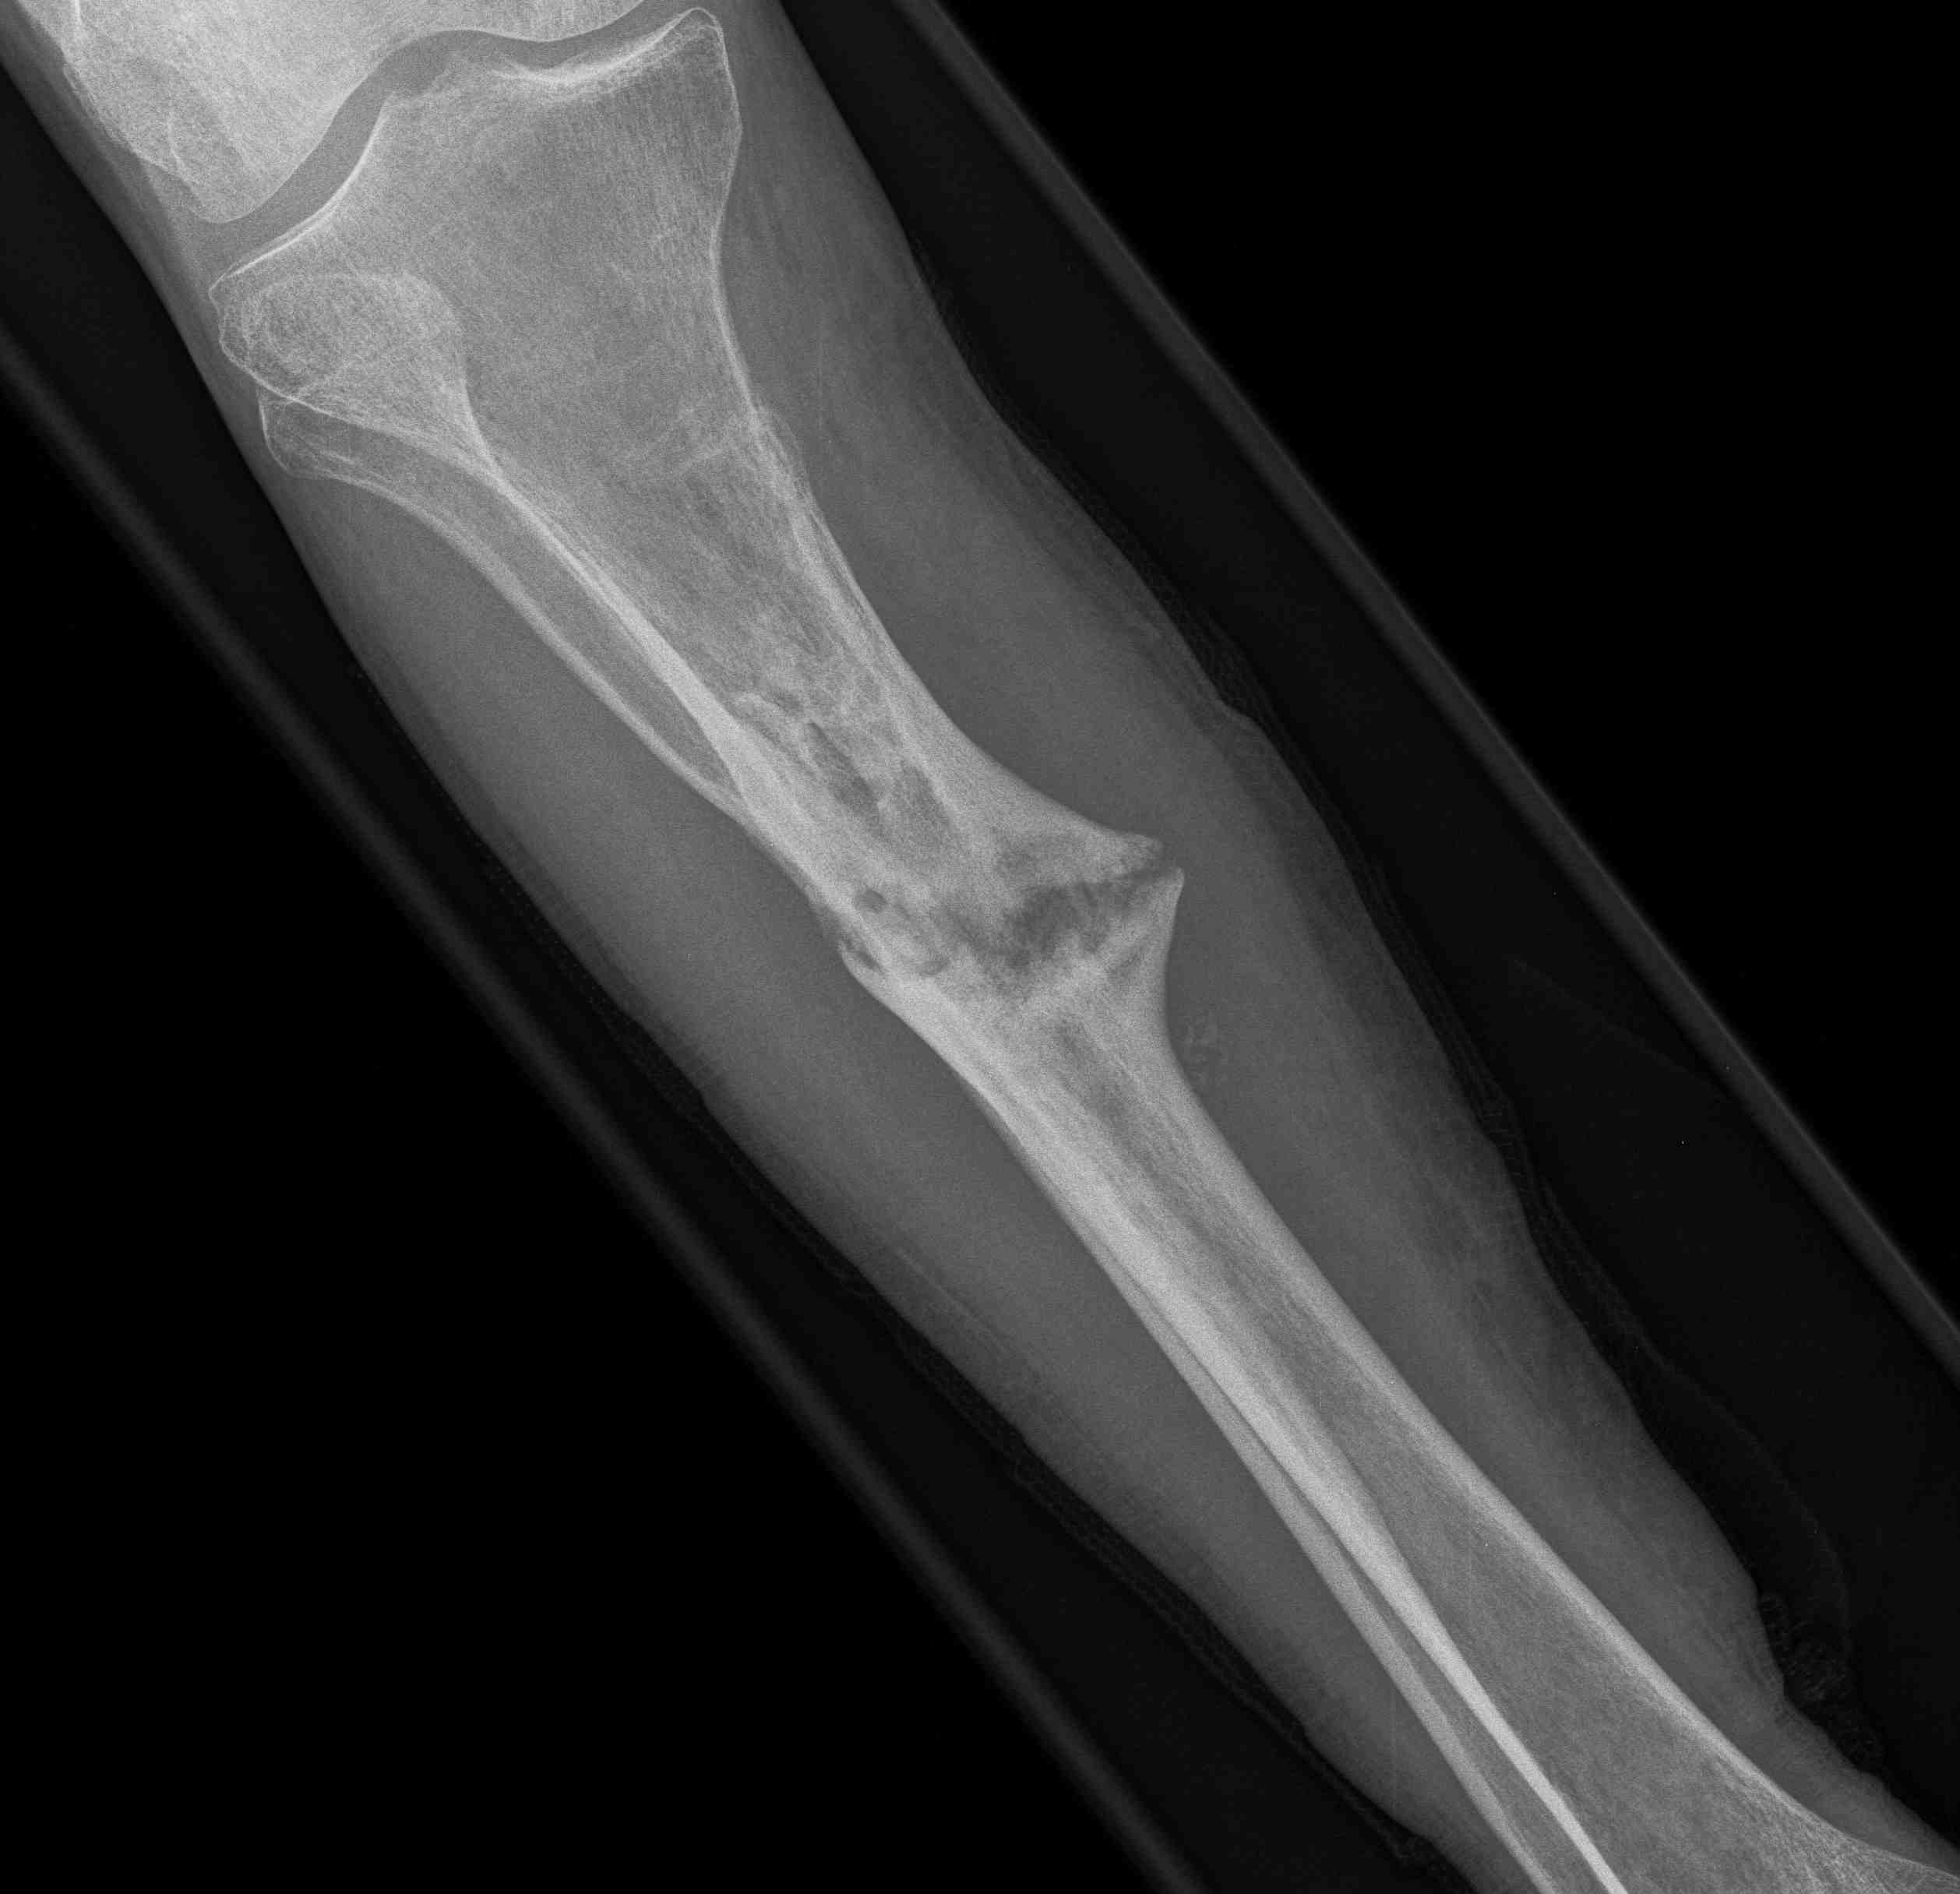

Segmental shaft fractures

Segmental tibia 1Segmental tibia 2

Corey et al J Orthop Trauma 2018

- 95 treated with IMN

- nonunion rate 10%

https://pubmed.ncbi.nlm.nih.gov/29432320/